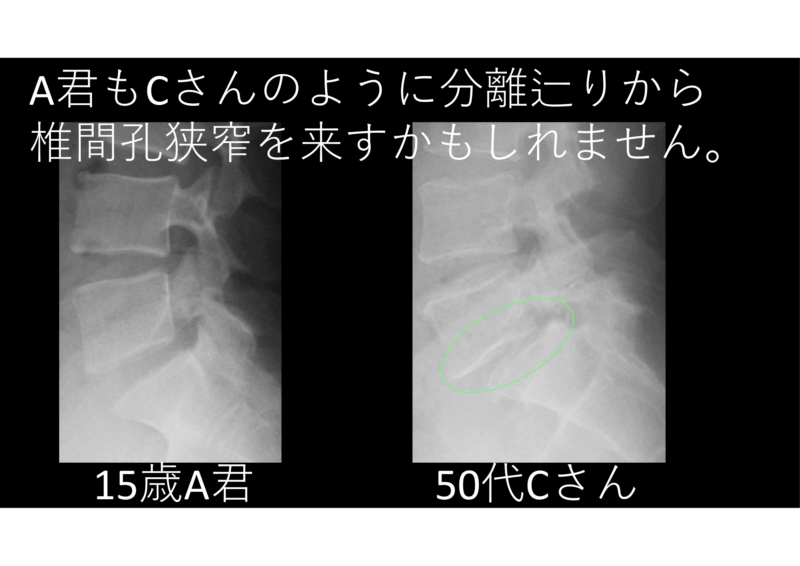

すべってしまったら、というところで50代男性Cさん登場。

15歳で分離確認、35歳から下肢しびれ、40歳から腰痛繰り返している。「しびれが全然良くならん」「そりゃあ、神経が圧迫されているからしびれが改善しないことは十分にありうるよ」

A君がCさんのように辷りを来さないように、しっかりと指導せねば。コラム読んでね。